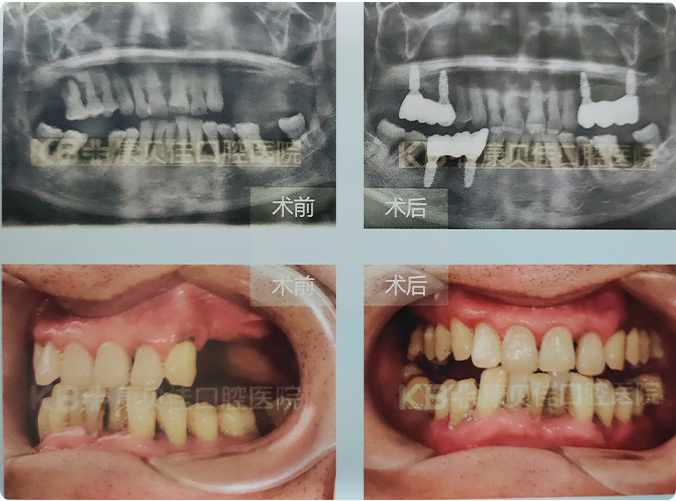

4年前全口多颗牙齿松动,在外院拔除,因为不放心外院种植技术,便到康贝佳找到任势雄博士。通过即刻拔除患牙,缺多种少的方式,重建上下颌后磨牙的咬合关系,找回一口好牙。

上颌种植4颗恢复7颗 下颌种植2颗恢复4颗